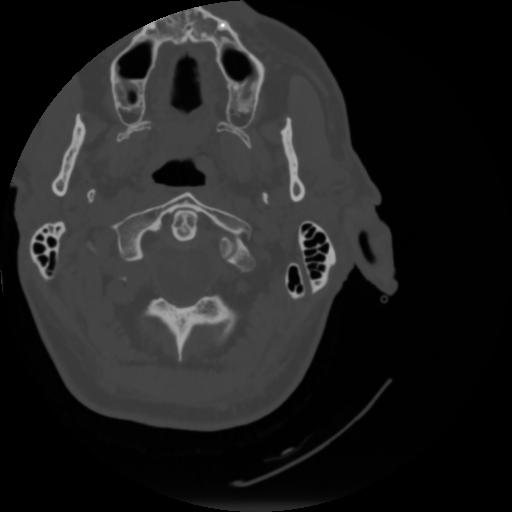

4 CEREBRO,,Vol,0.5,CEREBRO,,